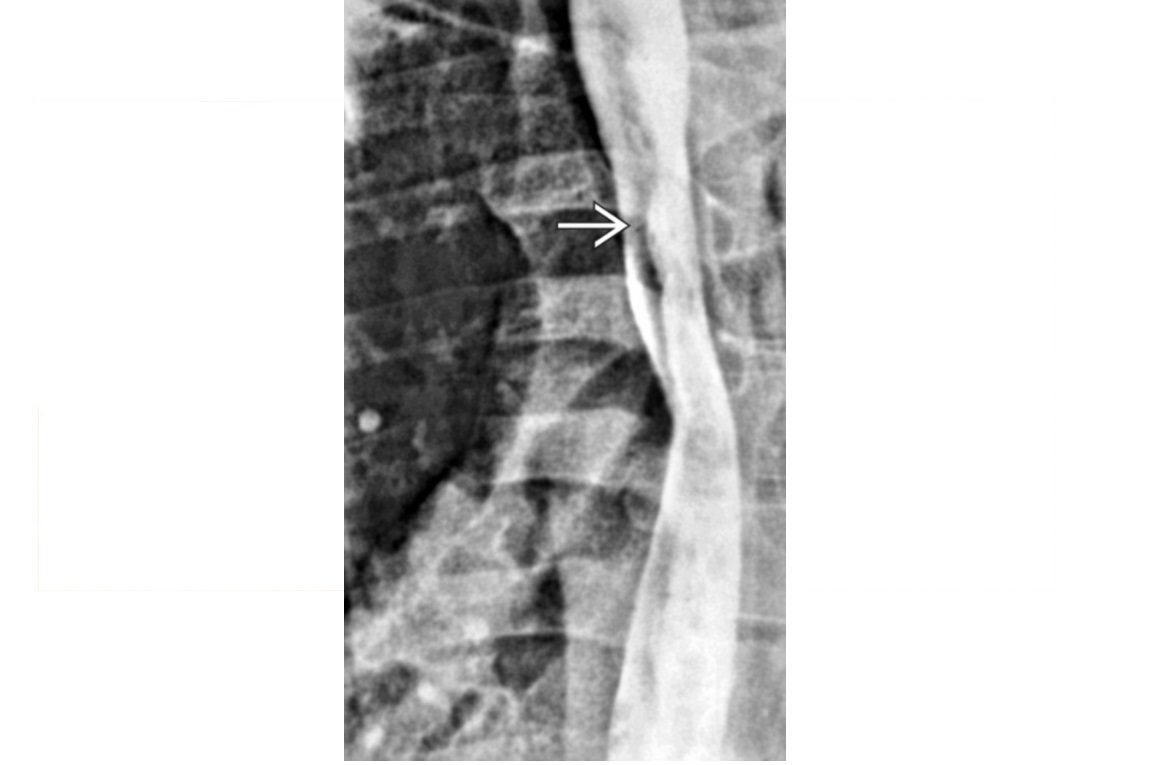

oesophageal scleroderma

-affects the Lower 2/3 (smooth muscle) with atony and peristalsis that begin caudally and moves cranially.

-Moderate dilatation of esophagus with fusiform stricture at lower end

Nb upper 1/3 to above aortic arch is normal (striated muscle)

Achalsia

- Grossly dilated whole oesophagus with smooth, beak-like tapering at lower end